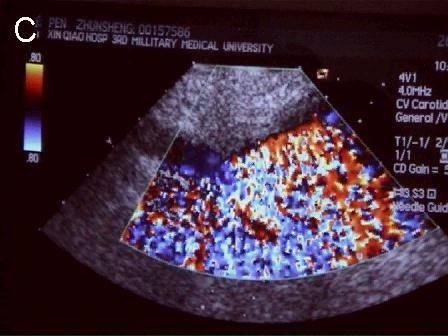

A 连接三联管及穿刺针准备 B 超声引导下注射针进入瘤腔底部(箭头处) C 经注射针注入盐水出现超声频闪现象; D 远端瘤腔内血栓逐渐形成; E 远端、近端瘤腔内血栓完全形成; F 术后足背动脉血流良好. 国内首家开展,例数最多,疗效肯定。此技术在全国推广应用。处于全国领先水平。